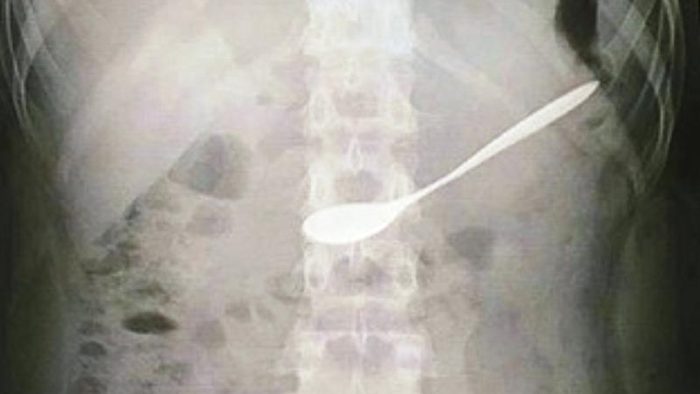

Sau khi tiếp nhận, nữ bệnh nhân được chuyển đến phòng Nội soi tiêu hóa của bệnh viện. Chụp X-quang, các bác sĩ phát hiện chiếc thìa nằm tại hang vị dạ dày của cô gái.

Các bác sĩ của bệnh viện đã tiến hành nội soi,  gắp chiếc thìa cà phê ra khỏi người nữ bệnh nhân này.